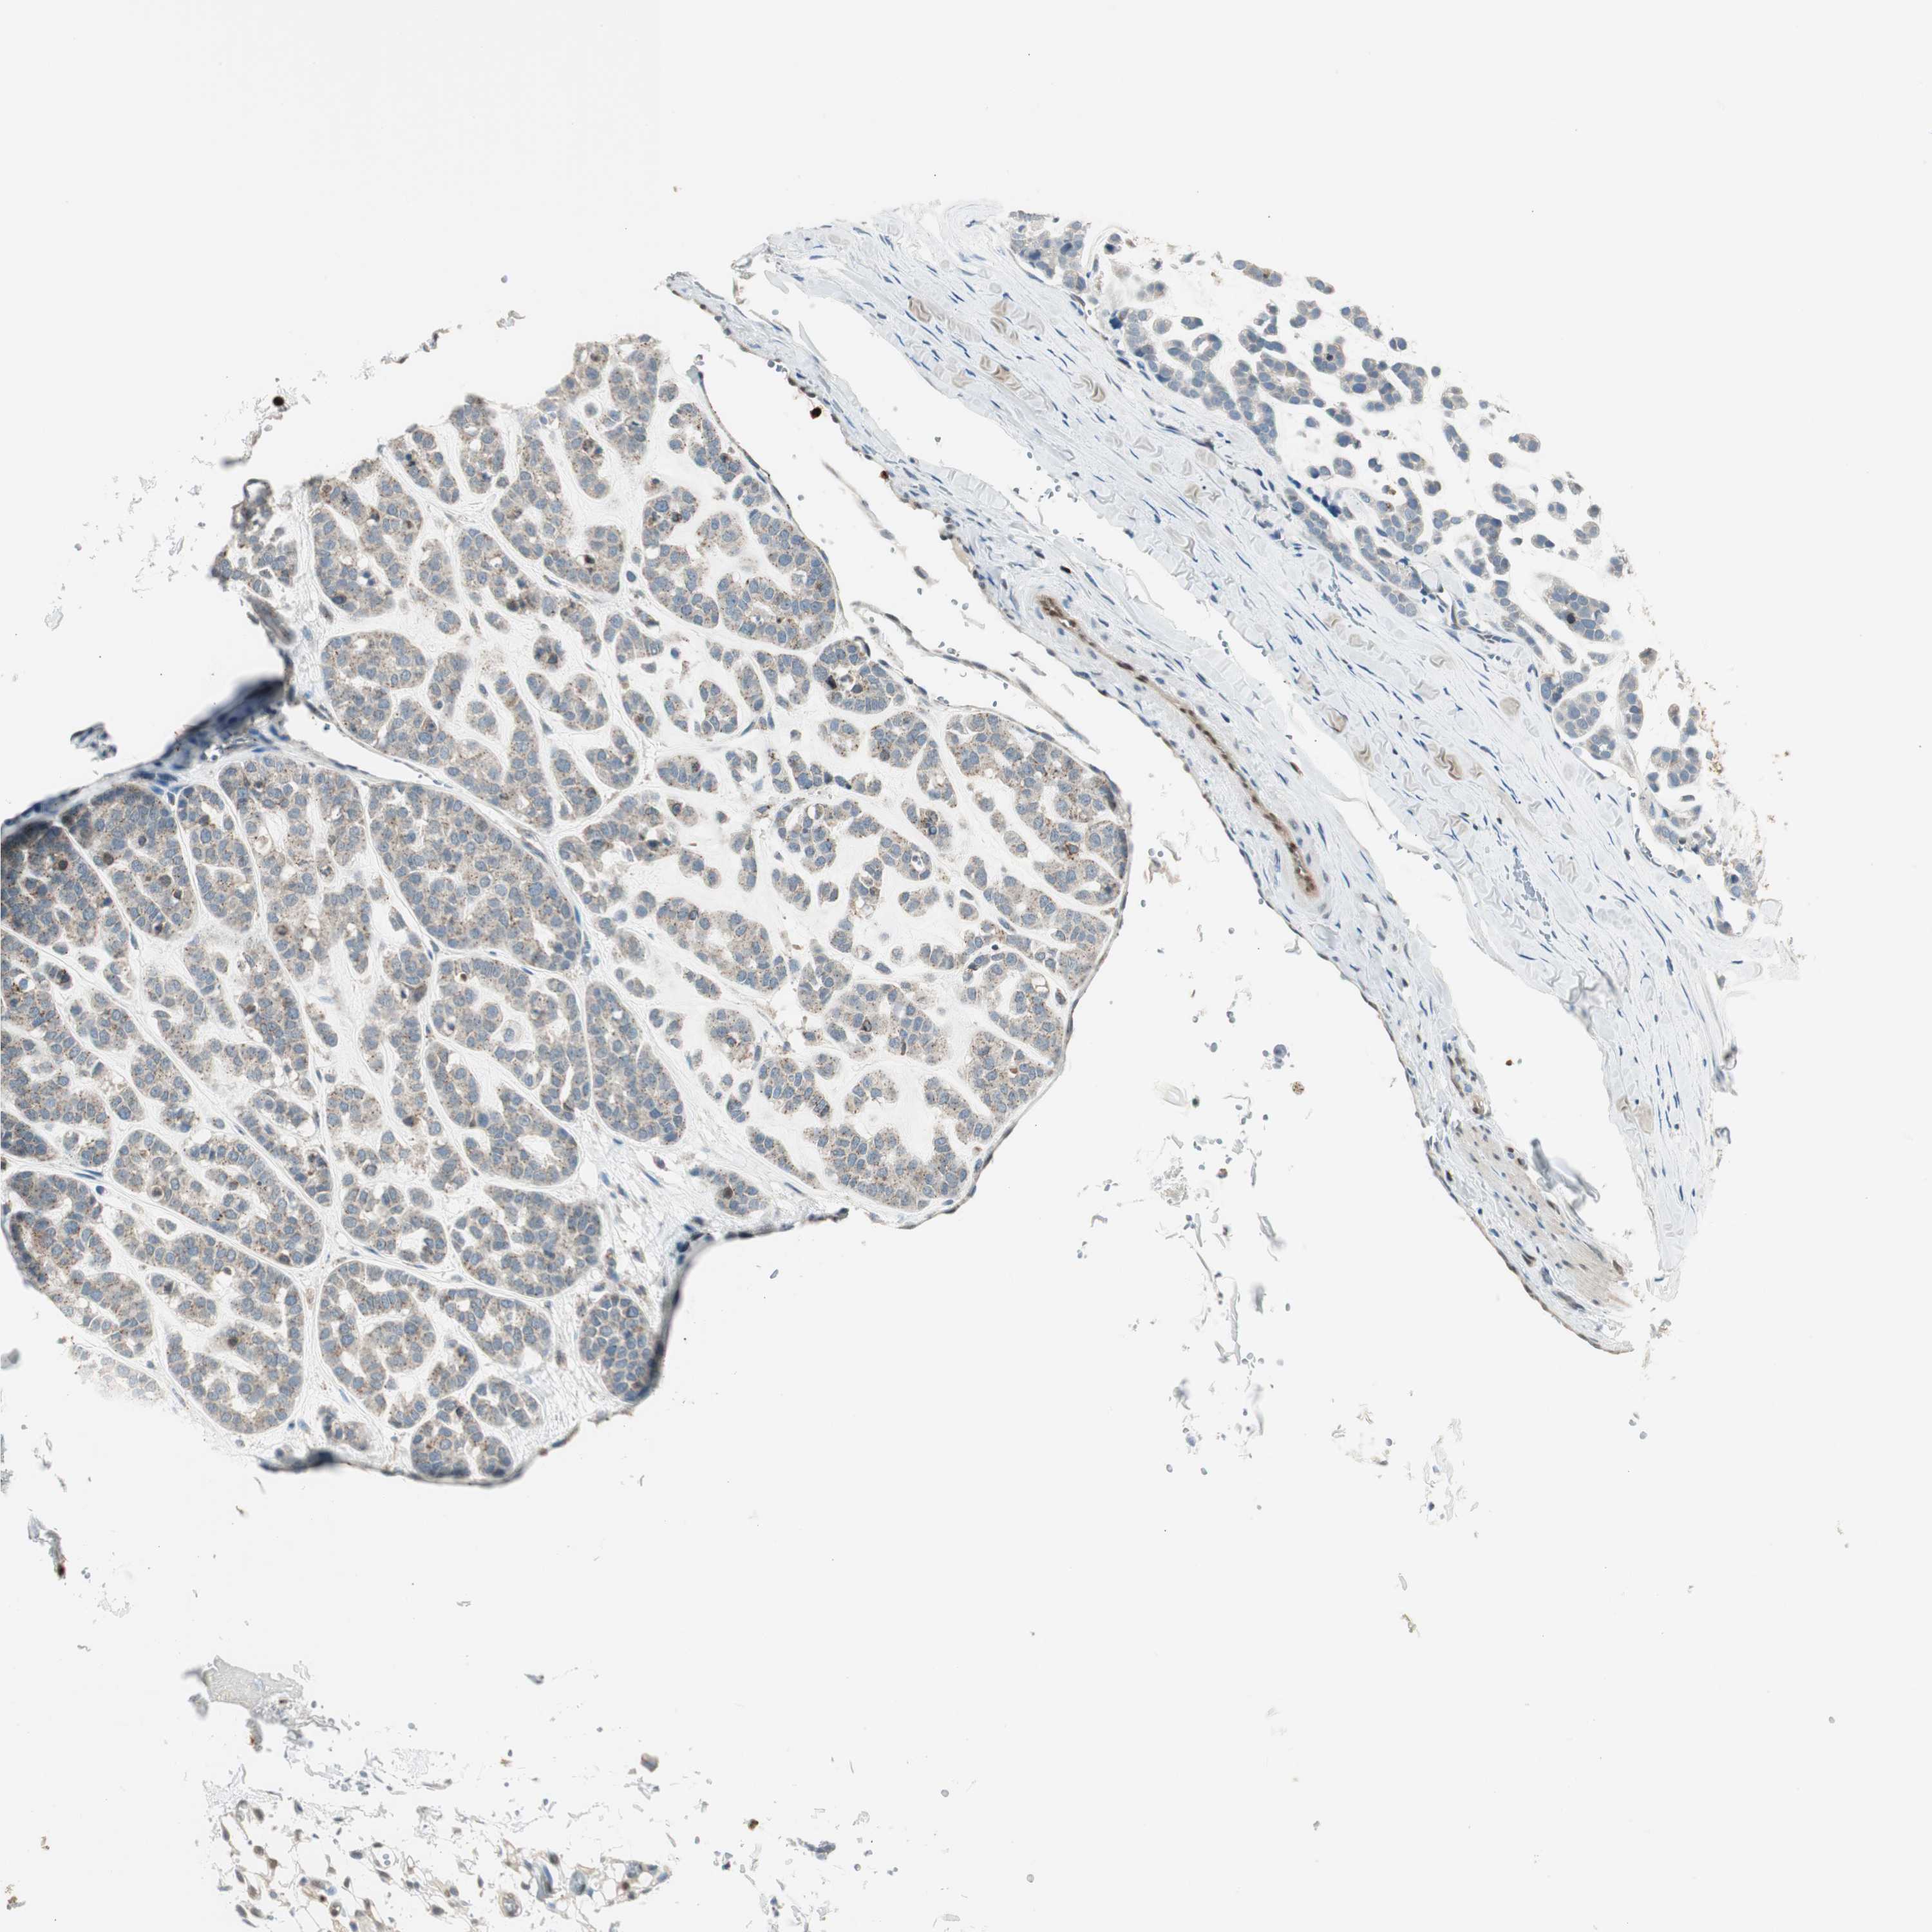

HEAD AND NECK CANCER - Protein expressioni

A mouse-over function shows sample information and annotation data. Click on an image to view it in a full screen mode. Samples can be filtered based on level of antibody staining by selecting one or several of the following categories: high, medium, low and not detected. The assay and annotation is described here.

Antibody stainingi

Antibody staining in the annotated cell types in the current human tissue is reported as not detected, low, medium, or high, based on conventional immunohistochemistry profiling in selected tissues. This score is based on the combination of the staining intensity and fraction of stained cells.

Each image is clickable and will lead to virtual microscopy that enables deeper exploration of all samples and also displays staining intensity scores, fraction scores and subcellular localization as well as patient and tissue information for each sample.

Antibody HPA008399

Antibody HPA017017

Antibody CAB015221

Staining

High

Medium

Low

Not detected

Intensity

Strong

Moderate

Weak

Negative

Quantity

>75%

75%-25%

<25%

None

Location

Nuclear

Cytoplasmic/membranous

Cytoplasmic/membranous,nuclear

Squamous cell carcinoma, NOS

Squamous cell carcinoma, metastatic, NOS

Adenocarcinoma, NOS

Adenoma, NOS